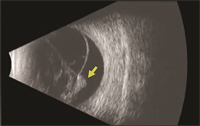

Viewing the retina with an indirect ophthalmoscope while the doctor applies gentle pressure to the eye (scleral depression) is the primary method for diagnosing retinal detachment. When view of the retina is obscured (blocked) by blood or dense cataract, B-scan ultrasonography can be used to determine the location and extent of a retinal detachment (Figure 2). To confirm whether there is subretinal fluid in the macula, optical coherence tomography (OCT) may be used.

Figure 2. B-scan ultrasound of a patient with PVR-related retinal detachment. A fixed retinal fold (yellow arrow) is seen with a cone-shaped retinal detachment. (Photo courtesy of Yale Fisher, MD. Retina Image Bank, © American Society of Retina Specialists.)